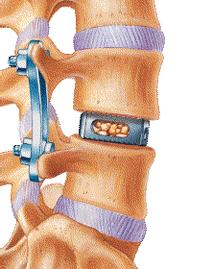

12 virginia spine institute reviews. The most common spinal disorders and conditions treated by sbi are cervical and lumbar spinal stenosis and disc herniation. 25.01.2019 · virginia spine institute has been providing elite spinal healthcare for over 25 years, improving the lives of over 85,000 patients suffering from back or neck conditions.

Today, under his leadership, virginia spine specialists strives to be on the cutting edge of minimally invasive procedures and techniques. A free inside look at company reviews and salaries posted anonymously by employees. Chairman, residency and fellowship program director. Uncover why virginia spine institute is the best company for you.